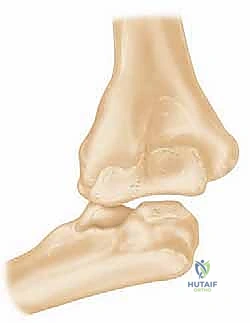

3. الالتحام المعيب للكسور (Malunion)

على عكس عدم الالتحام، في حالة "الالتحام المعيب"، يلتئم العظم المكسور بالفعل، ولكنه يلتئم في وضع خاطئ أو زاوية مشوهة.

* التأثير على الكوع: يؤدي هذا إلى تغيير الميكانيكا الحيوية للمفصل بأكمله. قد يحد من المدى الحركي بشكل كبير (لا يستطيع المريض فرد يده بالكامل أو ثنيها للمس كتفه)، وقد يؤدي إلى تشوه جمالي ووظيفي في الذراع (مثل اعوجاج الذراع للخارج أو للداخل).